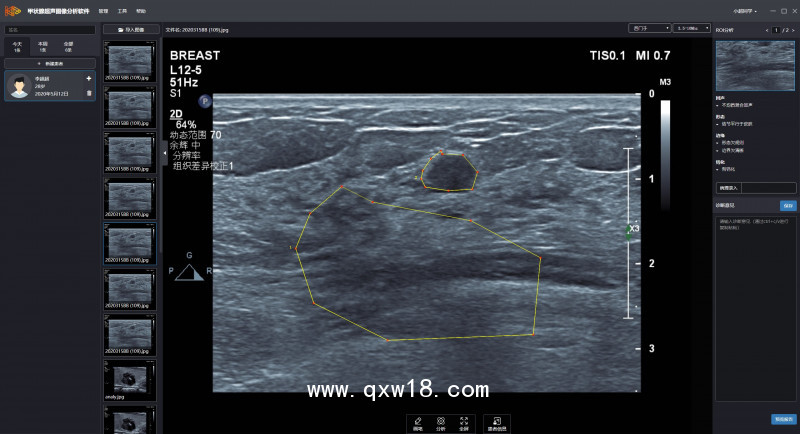

超聲影像輔助診斷系統(tǒng)產(chǎn)品說(shuō)明:

能提供輔助意見(jiàn)的自動(dòng)癌癥識(shí)別系統(tǒng),幫助及早發(fā)現(xiàn)癌癥,增加成功、及時(shí)治療的機(jī)會(huì)。

?利用先進(jìn)的深度學(xué)習(xí)神經(jīng)網(wǎng)絡(luò)結(jié)構(gòu),從二維超聲圖像中識(shí)別病變狀態(tài),其準(zhǔn)確度可達(dá)到甚至超過(guò)有經(jīng)驗(yàn)的超聲醫(yī)生;

?在訓(xùn)練深度學(xué)習(xí)神經(jīng)網(wǎng)絡(luò)模型的時(shí)候,選取了醫(yī)院常用的各種型號(hào)的超聲機(jī)采集的圖像,保證訓(xùn)練模型在臨床實(shí)踐中有更好和更廣泛的適用性;

?為不同器官(如甲狀腺、乳腺、肝、卵巢和膀胱)的腫瘤分類開(kāi)發(fā)一個(gè)通用的深度學(xué)習(xí)神經(jīng)網(wǎng)絡(luò)結(jié)構(gòu),有望建立更可靠的基于機(jī)器的診斷模型,并易于技術(shù)維護(hù)和支持;

?采用計(jì)算機(jī)視覺(jué)領(lǐng)域的最新技術(shù),使用深度學(xué)習(xí)神經(jīng)網(wǎng)絡(luò)檢測(cè)主要腫瘤特征,以協(xié)助醫(yī)生對(duì)腫瘤特征的描述,并為醫(yī)生的最終診斷決策提供支持。